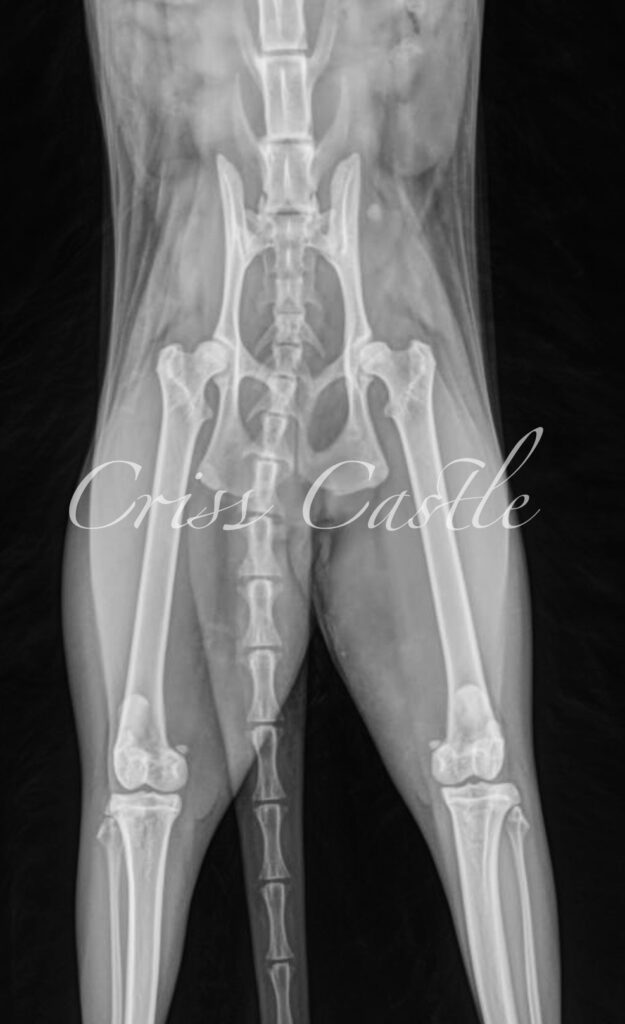

Hip X-Ray Results

Below are the current hip x-ray results for each Criss Castle breeding cat.

Note that as the cats continue to grow, this page may be updated with new results.